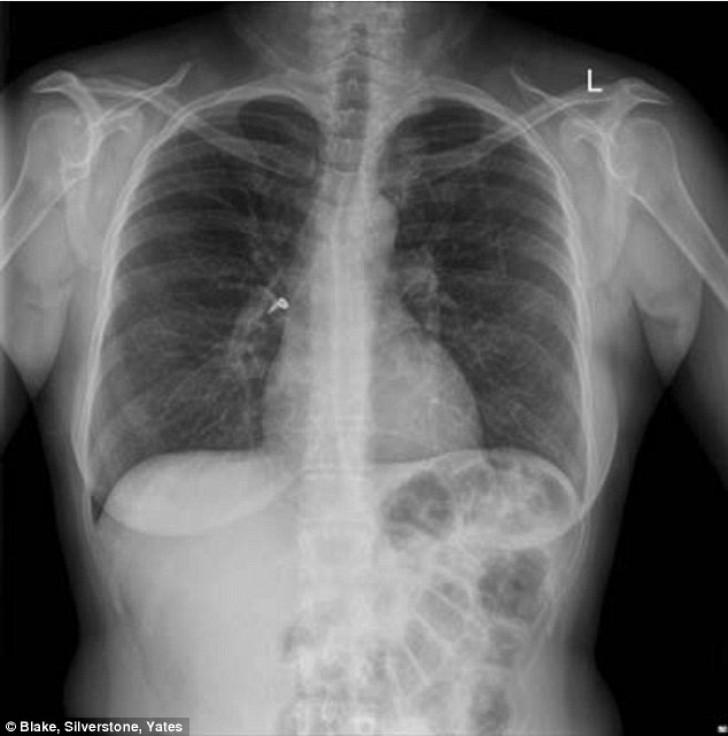

Femeie cu cercel în plămân, caz neobișnuit. Obiectul a fost inhalat din greșeală